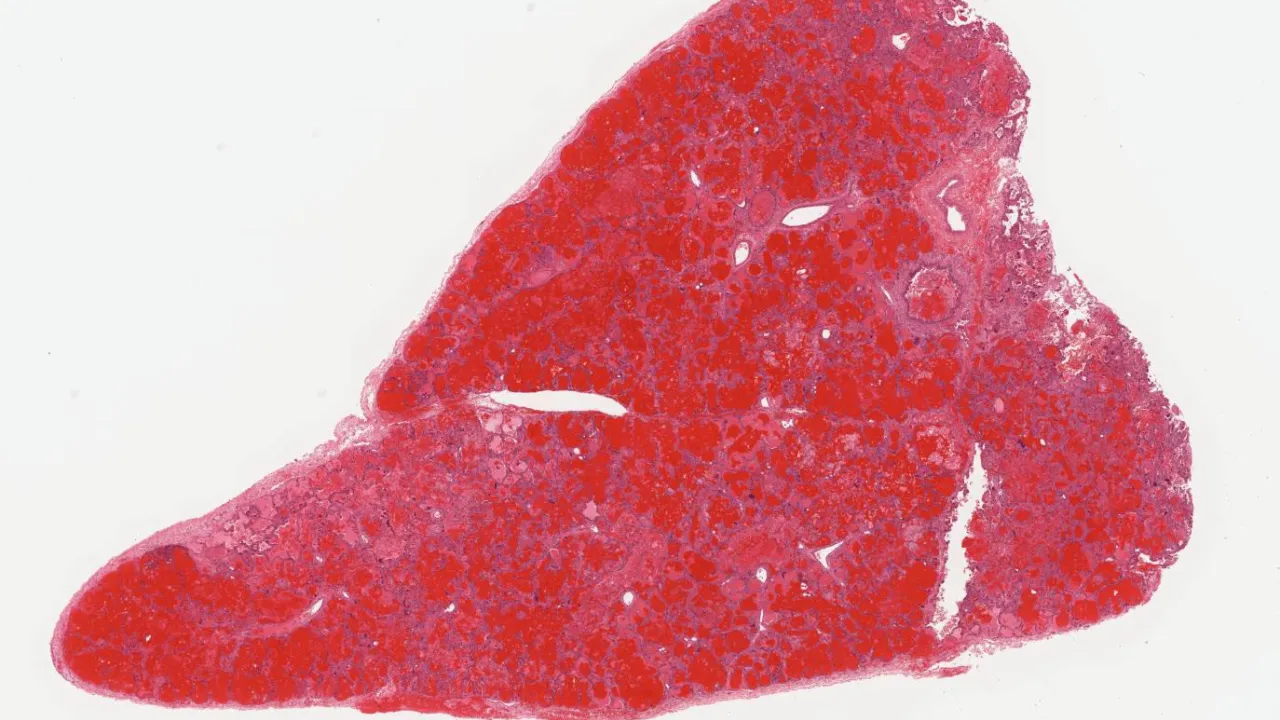

Lung

Lung, Mucoepidermoid carcinoma, low grade, H&E Stain

Lung, Pneumoconiosis

Lung, Adenocarcinoma

Trachea, Small cell carcinoma

Lung, Talc granulomata

Lung, Metastatic adenocarcinoma

Lung, Pneumocystis jirovecii

Pleural cavity, Twin reversed arterial profusion sequence

Lung, Silicosis

Lung, Small cell carcinoma

Pleura, Malignant mesothelioma, biphasic type

Lung, Pneumocystis jirovecii pneumonia

Lung, Parainfluenza pneumonia

Lung, surfactant dysfunction disorder

Lung, Malignant mesothelioma

Lung, Langerhans cell histiocytosis

Lung, Usual interstitial pneumonia

Lung, Cryptogenic organizing pneumonia

Lung, Chronic eosinophilic pneumonia

Lung, Nonspecific interstitial pneumonia, cellular pattern